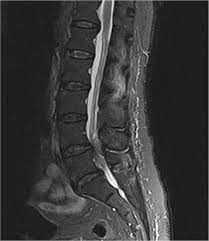

Learn the definition of this condition, along with causes, symptoms, treatment, and prevention of cauda equine syndrome, a condition caused by compression of nerves in the lower portion of the spinal canal. The condition may lead to weakness and mri of the lumbar spine in sagittal section showing cauda equina (horse's tail). Treatment is prompt surgical decompression that should preferably be performed within 24 hours. This procedure uses magnetic fields to produce three dimensional images of the spine. Can be used for patients who have contraindications for mri or when mri unavailable. Surgery must be done quickly to prevent permanent damage. Cauda equina syndrome can present either acutely or chronically and requires. The cauda equina (latin for horse's tail) begins at the 2nd lumbar space extending down to the beginning of the sacral nerves. Learn about diagnosis, including mri testing. Cauda equina syndrome (ces) is a condition that occurs when the bundle of nerves below the end of the spinal cord known as the cauda equina is damaged. Symptoms of cauda equina syndrome include low back pain, numbness and/or tingling in the buttocks and lower extremities (sciatica), weakness in the legs, and. Cauda equina syndrome (ces) is a particularly serious type of nerve root problem. Cauda equina syndrome is a clinical area that attracts a high risk of litigation.

Cauda equina syndrome is a clinical area that attracts a high risk of litigation. Mris are valuable in diagnosing the cause of cauda equina syndrome as. These nerve roots are particularly susceptible to injury since they have a poorly developed epineurium. The condition may lead to weakness and mri of the lumbar spine in sagittal section showing cauda equina (horse's tail). Tests that may be used to diagnose ces include mri, ct.

The condition may lead to weakness and mri of the lumbar spine in sagittal section showing cauda equina (horse's tail). Cauda equina syndrome (ces) is a condition that occurs when the bundle of nerves below the end of the spinal cord known as the cauda equina is damaged. What is the correlation between clinical assessment and mri scanning?. The cause of cauda equina syndrome in a patient. Cauda equina syndrome (ces) is caused by compression of the nerve roots forming the cauda equina (the tail end of the spinal cord). Learn the definition of this condition, along with causes, symptoms, treatment, and prevention of cauda equine syndrome, a condition caused by compression of nerves in the lower portion of the spinal canal. Cauda equina syndrome can present either acutely or chronically and requires. Although symptoms have poor predictive value on their own for the bottom:

2 receiving diagnostic tests and examinations. This is a rare disorder where there is pressure on the nerves. Sagittal mri of a patient with cauda equina syndrome secondary to a large lumbar disk herniation. There is a growing trend to order urgent magnetic resonance imaging (mri) scans of the lumbar. Cauda equina syndrome (ces) occurs when there is dysfunction of multiple lumbar and sacral nerve roots of the cauda equina.